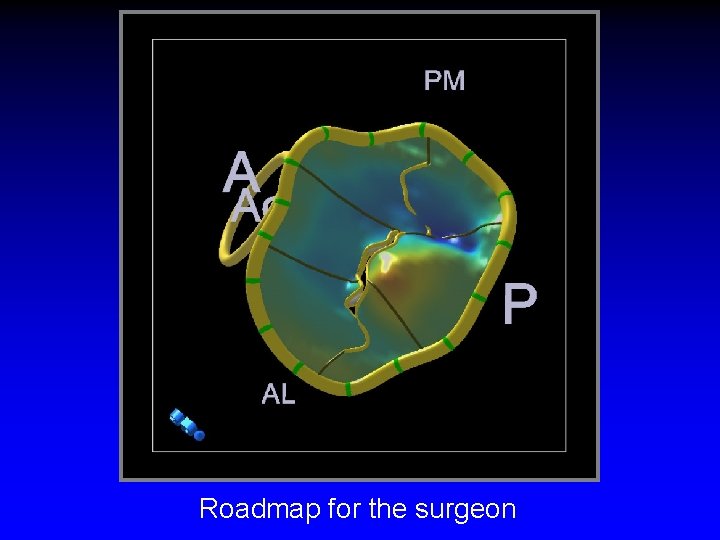

Roadmap for the surgeon

Mitral Valve Repair Information Required by Surgeon • Exact lesion(s) - affected segment(s) • Extent • Degree of calcification (leaflet/annulus) • Dilatation/size of annulus